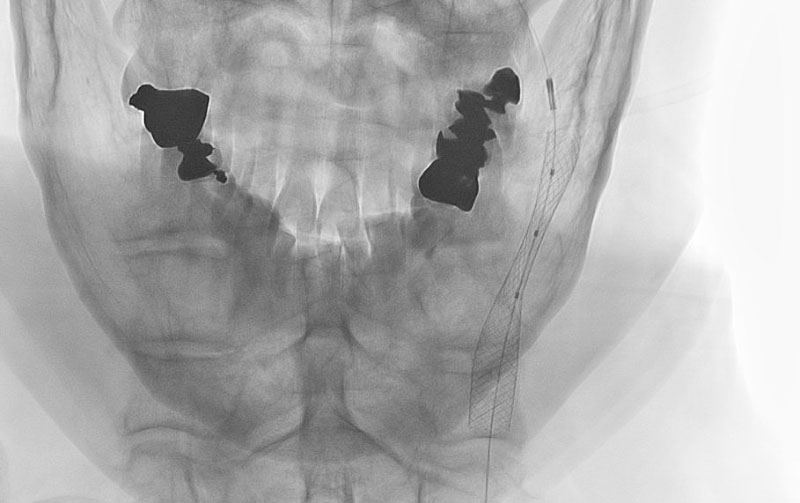

1619

'26年3月11日

左内頚動脈狭窄症

70代

大阪府の病院

手術写真

治療

前